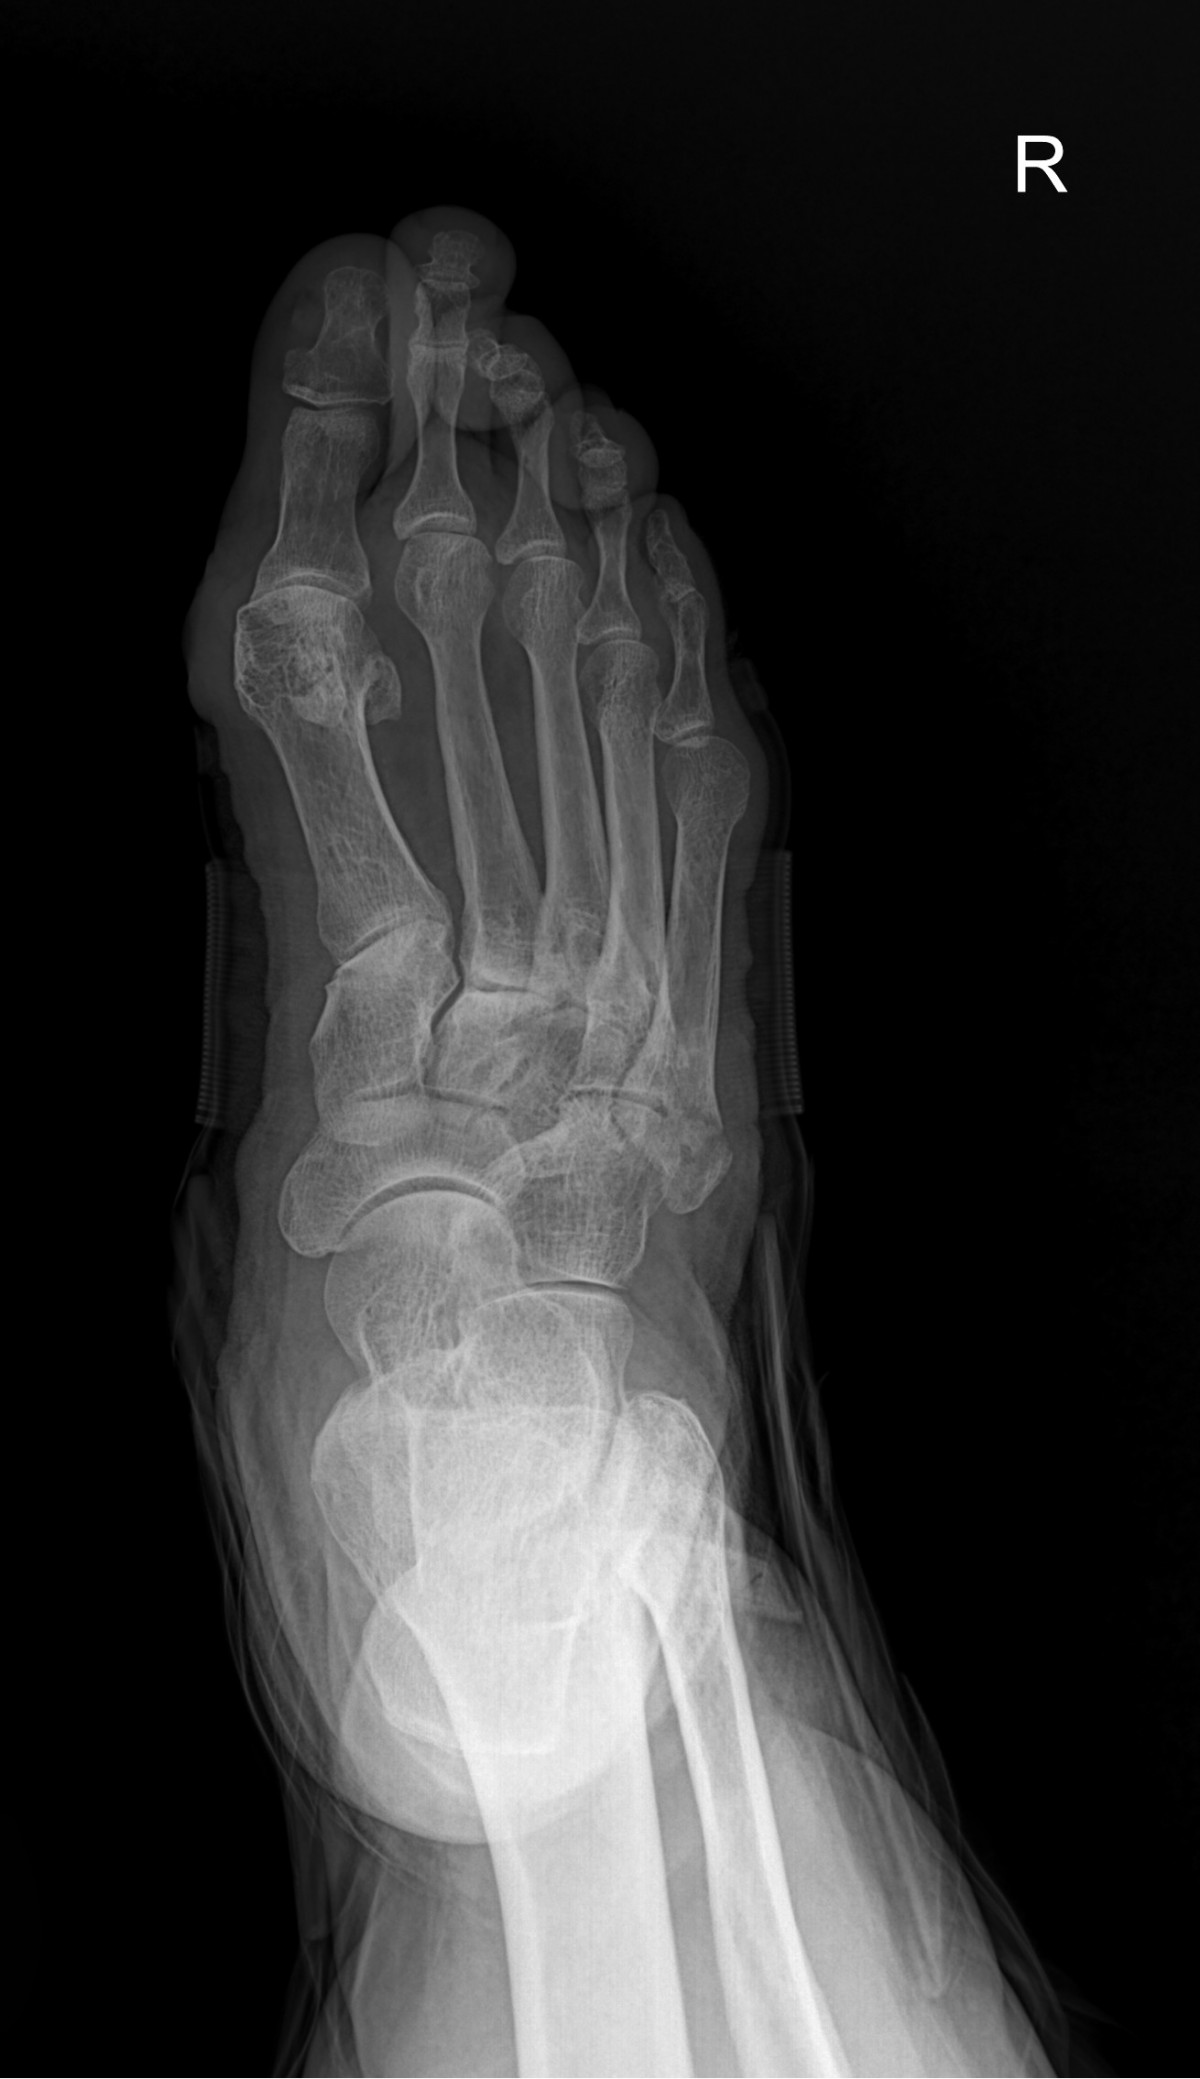

이재상원장님 무지외반증 및 발등 골절 수술 김순O 환자

dae765e4d9ac96aee867c9d6292d8784_1758002450_5412.jpg